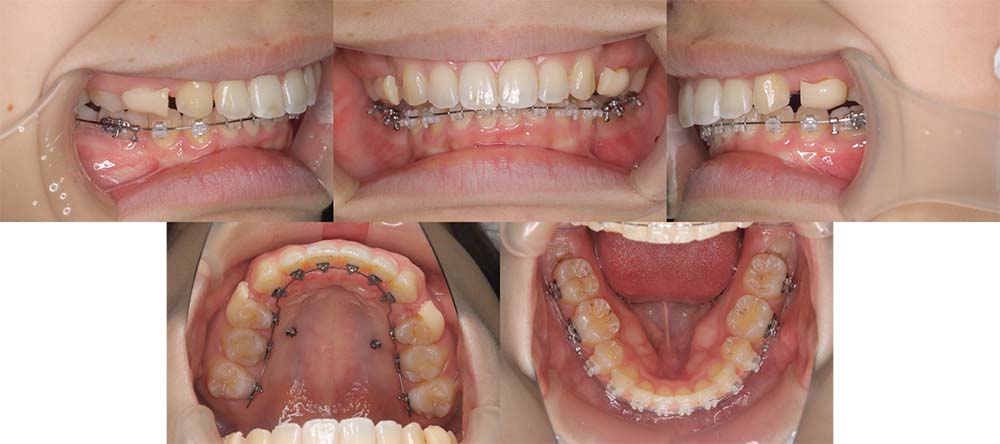

| 症例分類 | 上顎前突、叢生、シザースバイト |

| 診断名 | 右上7のシザーズバイトを伴う上下重度叢生skeletal2 |

| 主訴 | 歯並びが悪くて全体的にガタガタ |

| 年齢 | 19歳11ヶ月 |

| 性別 | 女性 |

| 抜歯部位 | 上顎左右と右下の第一小臼歯、左下の第二小臼歯(4本)、上顎右側第二大臼歯 |

| 使用装置 | 裏側のワイヤー装置 |

| 治療期間 | 2年11ヶ月(5ヶ月程度来院出来ない期間あり) |

| 保定装置 | 固定式保定装置、取り外し式保定装置(8時間) |

| 費用 |

[検査・診断料] ¥49,500 [基本施術料] ¥1,331,000 [調整料] ¥5,500/回 [抜歯] ¥5,500/本 [保定装置] ¥55,000(税込) 抜歯や虫歯治療は他院にて費用が別途かかります。(抜歯¥4,000〜10,000/本)

上下の重度叢生と上の歯が前方にあり上顎両側の第一小臼歯と下顎右側第一小臼歯、下顎左側第二小臼歯、上顎右側第二大臼歯(上顎右側親知らずを咬合に使用)を抜去して上下リンガルで治療を行いました。 左上の第二大臼歯部の咬合が深かったため、一時的に頬側に装置をつけさせて頂きました。裏側に装置を装着すると噛み合わせを浅くするためのバイトアップがかなりの量が必要になり咬みづらくなってしまうためです。

5ヶ月程度来院が出来なかった期間がありましたが、問題なく治療を終了することができました。